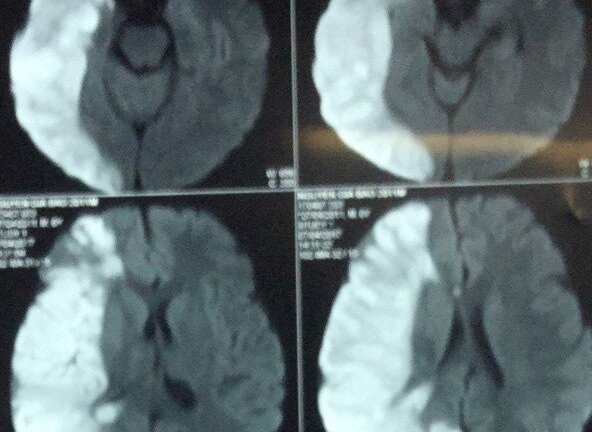

Thông tin bệnh viện Nhi đồng 2 cho biết, có hai bệnh nhi liên tục lên những cơn đau đầu, cha mẹ cho trẻ nhập viện điều trị nhưng không dứt điểm dẫn đến trẻ mang bệnh lý mạch máu não hiếm gặp.